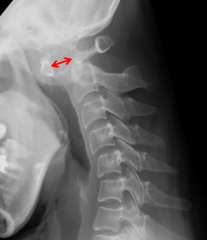

- 頸椎を横から見たレントゲン写真

まず、頸椎の不安定性の評価には単純X線が用いられます。神経障害を認めた場合、もしくは単純X線像で頸椎病変を疑った場合にはCTやMRIの適応となります。CTは骨びらんや脱臼、関節強直などの評価に有用です。脊髄や神経根の圧迫の有無の評価にはMRIが有用です。